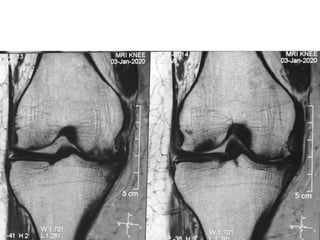

The document presents a detailed case study of a patient with transient osteoporosis of the hip (TOH) and spontaneous osteonecrosis of the knee (SONK) treated at Choithram Hospital & Research Centre in India. Over 20 years, the patient experienced multiple episodes of TOH and SONK with no history of trauma or co-morbidities, resulting in resolutions and recurrences of conditions. The information is intended for orthopedic surgery students and highlights personal experiences and case collections, with a disclaimer regarding content usage and potential controversies.